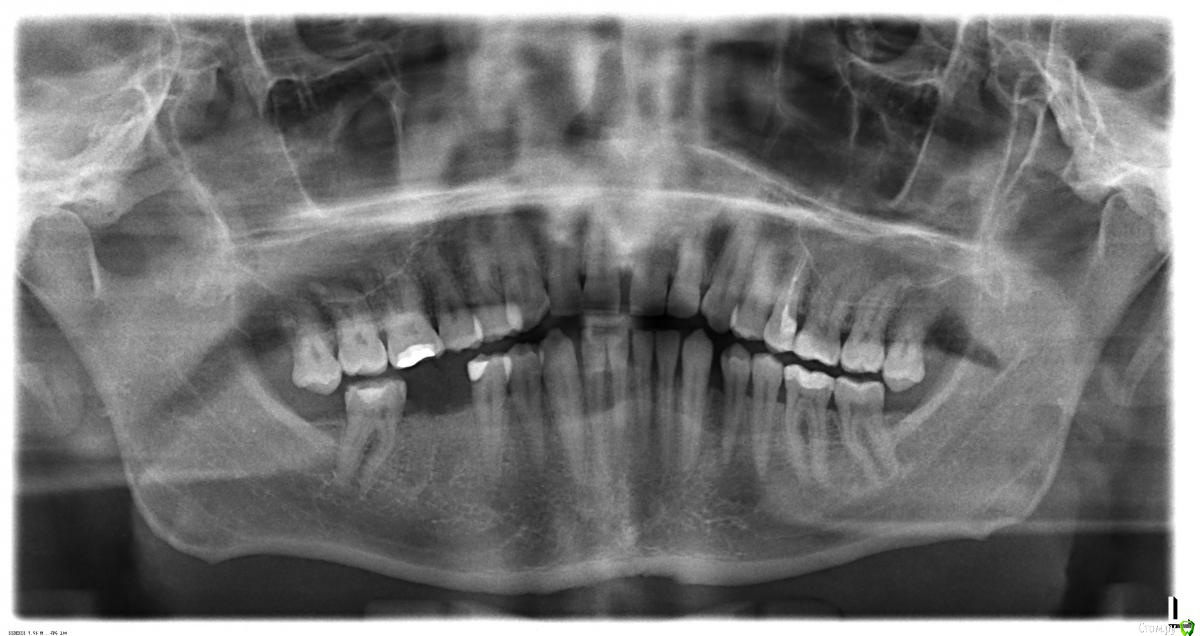

skyw Опубликовано 29 октября, 2017 Поделиться Опубликовано 29 октября, 2017 (изменено) Имеются два зуба мудрости сверху. Здоровые. но снизу нет антагонистов (и вероятно уже не будет раз до 40 лет не выросли). В связи с отсутствием нижних верхние несколько опустились судя по снимку. Врач говорит, что пользы от них нет, а скорее вред - во-первых лишний карман (между 8 и 7 сверху), что увеличивает шансы на кариес нужных седьмых зубов. И плюс в связи с опусканием 8-ых они краями травмируют края нижних седьмых.Как думаете удалить ? Врач говорит, что процедура быстрая, не травматично. И если да, то можно сразу с обеих сторон удалить, чтобы за один раз отмучиться ? Изменено 29 октября, 2017 пользователем skyw Ссылка на комментарий